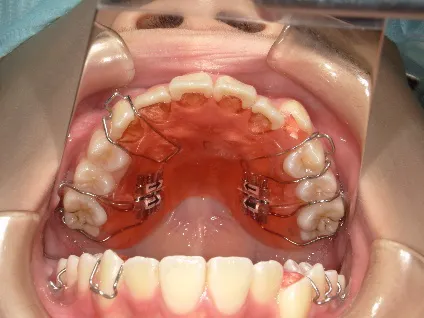

治療中③中1:非抜歯治療の診断で、上顎に歯の生えるスペースをつくるため上顎左右6をプレートで遠心移動し、隙間ができた時点

マルチブラケット法へ移行します

*マルチブラケット法移行前

| 行ったご提案・診断内容 | 生え変わりが終わってなくマルチブラケット法による咬合治療には早い時期のため、顔立ちの成長を促す目的で歯列弓(アーチ)の拡大と前歯を並べながら永久歯が生えるのを待ち、咬合治療開始時に再診断で抜歯、非抜歯を最終検討する提案をしました。 再診断時(写真②)、歯列の拡大と上顎前歯の並べ替えはされていましたが八重歯となったため抜歯、非抜歯を検討しました。 口元は特に問題がなく非抜歯で八重歯を改善するためのスペースを作ることが可能なため非抜歯治療を提案しました。 治療は、 ・拡大および上顎左右6を遠心移動させてスペースを作る 予定装置 |